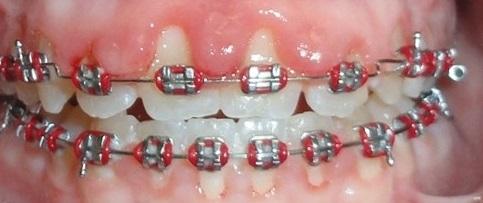

Bracket is defined as “An attachment on a fixed *orthodontic appliance. They are *bonded onto teeth with a *composite material.” These are the metal attachments that help move the teeth.

Hooks are small metal rods that are attached to the bracket which allows elastics to be attached to them.